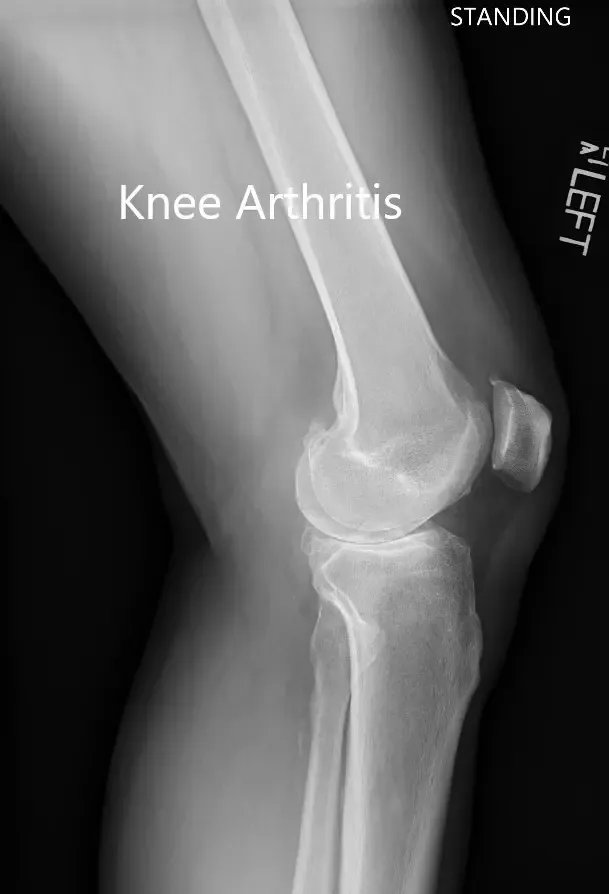

Imaging study revealed severe osteoarthritis of both knees. Considering her lifestyle limiting knee pain, she was offered bilateral custom total knee replacement. Risks, benefits, and alternatives were discussed thoroughly with her and her daughter. She agreed to go ahead with the surgery.

Preoperative X-ray showing the lateral view of the left and the right knee joint